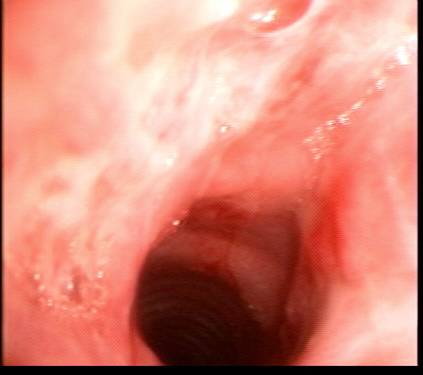

On the next screen you will see seelcted bronchoscopy pictures.

Describe bronchoscopy.